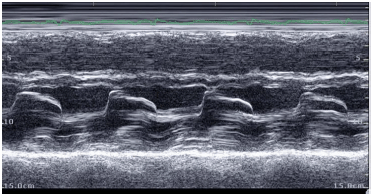

Assinale a classificação de Carpentier para a imagem abaixo.

Oficial Médico - Cardiologia/Ecocardiografia